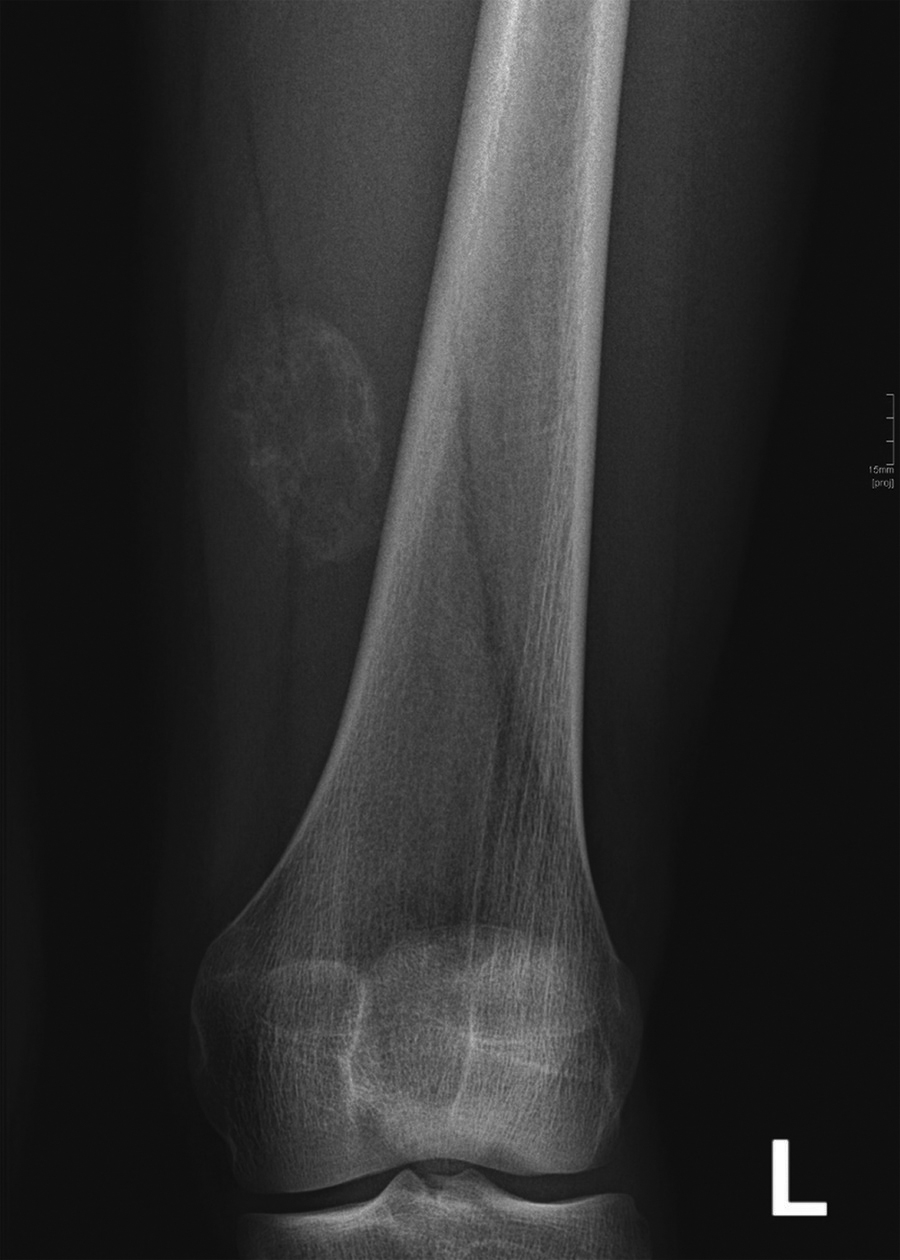

The diagnosis of myositis ossificans was suspected. A radiograph at this time showed no abnormalities. A follow-up radiograph 4 weeks later demonstrated peripheral calcifications, confirming the diagnosis (Figure 3).

Figure 3

Radiograph of myositis ossificans shows progressive, oval, intramuscular ossification.

The lesion might be mistaken for a sarcoma, particularly in the first and intermediate stages. The radiological key to the diagnosis is progressive peripheral bone formation, usually visible after 2 to 4 weeks on a radiograph (Figure 3), computed tomography (CT) or ultrasound.